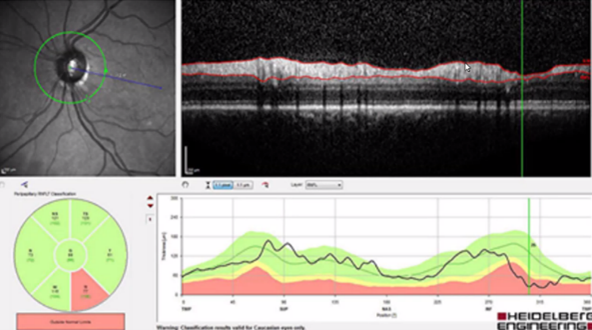

Glaukom

Vilken undersökning är detta och vad visar bilden?

A

Bedömning av papill/nervfiberlager (även gangliecellslagret)

o OCT - RNFL (retinal nerve fiber layer) peripapillärt, retinala nervfiberlagret (axoner): Tjocka buntar som ska följa kärlen (klarar sig där). Eldsflammor är nerfiberbuntar, släcks ut och förtunnas vid glaukom (övre eller nedre släcks oftast först)

o Mätning av ring runt nervcellslagret: Dippar ner under det gröna, indikerar en glaukomskada